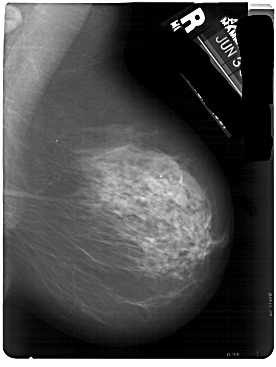

A_1824_1.RIGHT_CC

RIGHT_MLO LINES 5491 PIXELS_PER_LINE 4126 BITS_PER_PIXEL 12 RESOLUTION 43.5 NON_OVERLAY